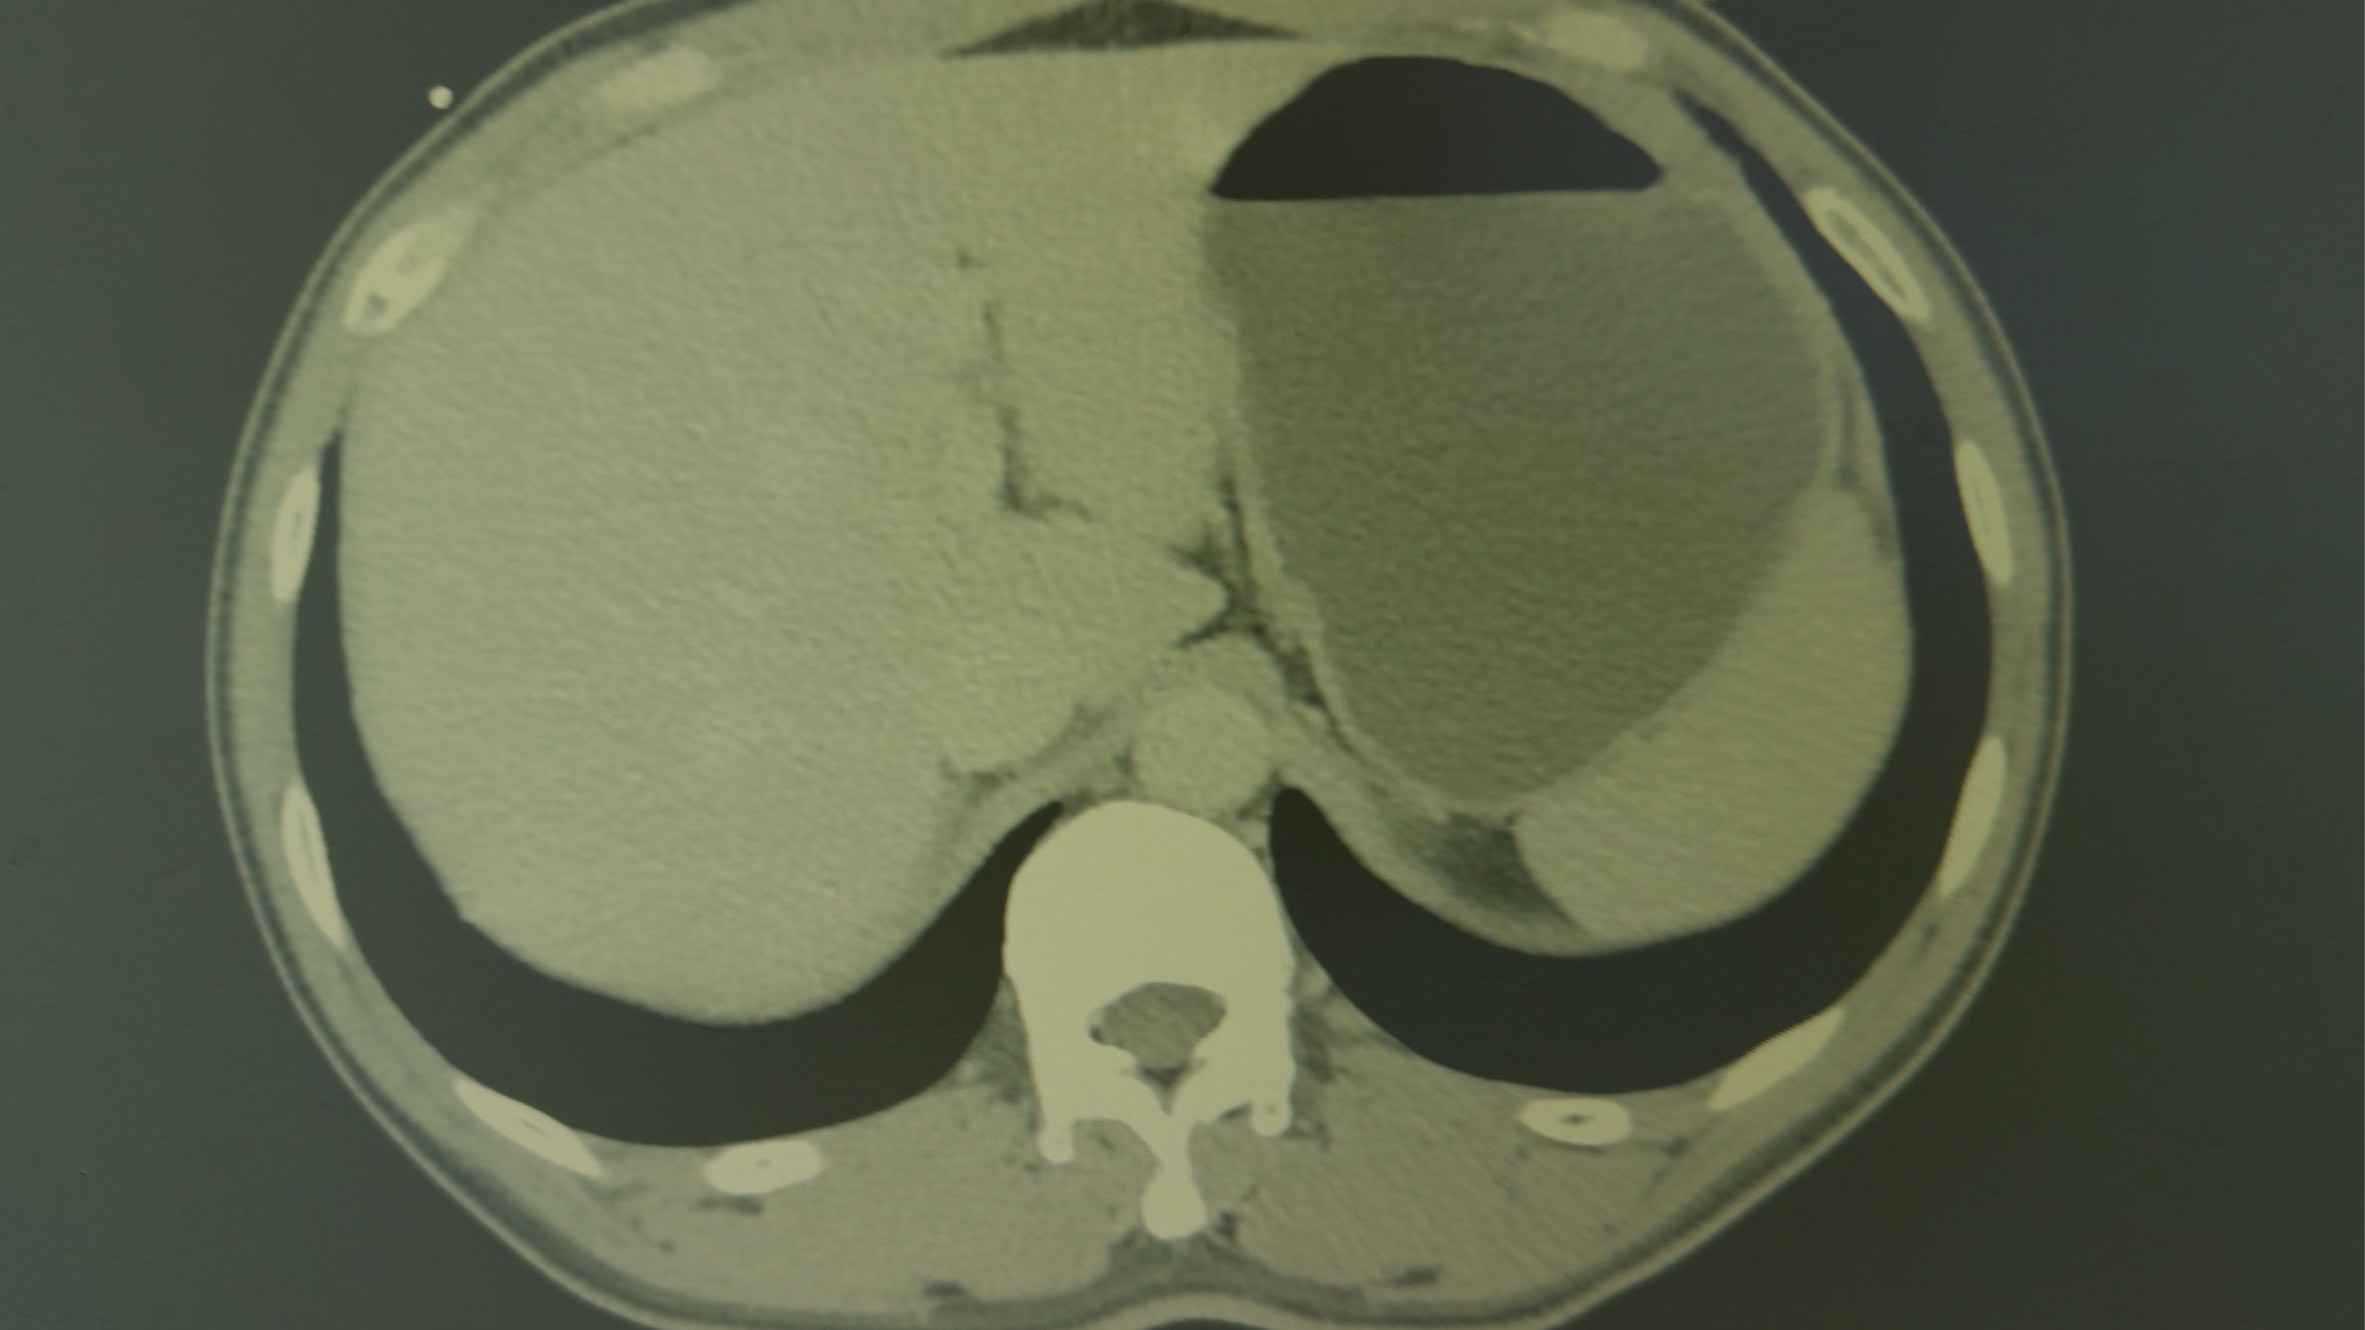

【检查】:门诊行光谱Ct检查:左肾低回声,考虑囊肿,建议进一步检查。胃及十二指肠扩张。前列腺增生。

但查体与体征不符,普通光谱Ct检查无阳性表现让我精神紧绷,立刻想到了夹层、肠系膜血管栓塞、肾梗死等血管疾病,嘱测量左侧上肢血压163/98mmHg,右侧上肢162/98mmHg。急查血常规、肾功、淀粉酶、心梗三项、血凝等,有异常的只有血糖8.0mmol /L。

左肾上动脉栓塞 肾梗死(内心os 不是我的活,但是县级人民医院,没有分科那么细,只好收下)